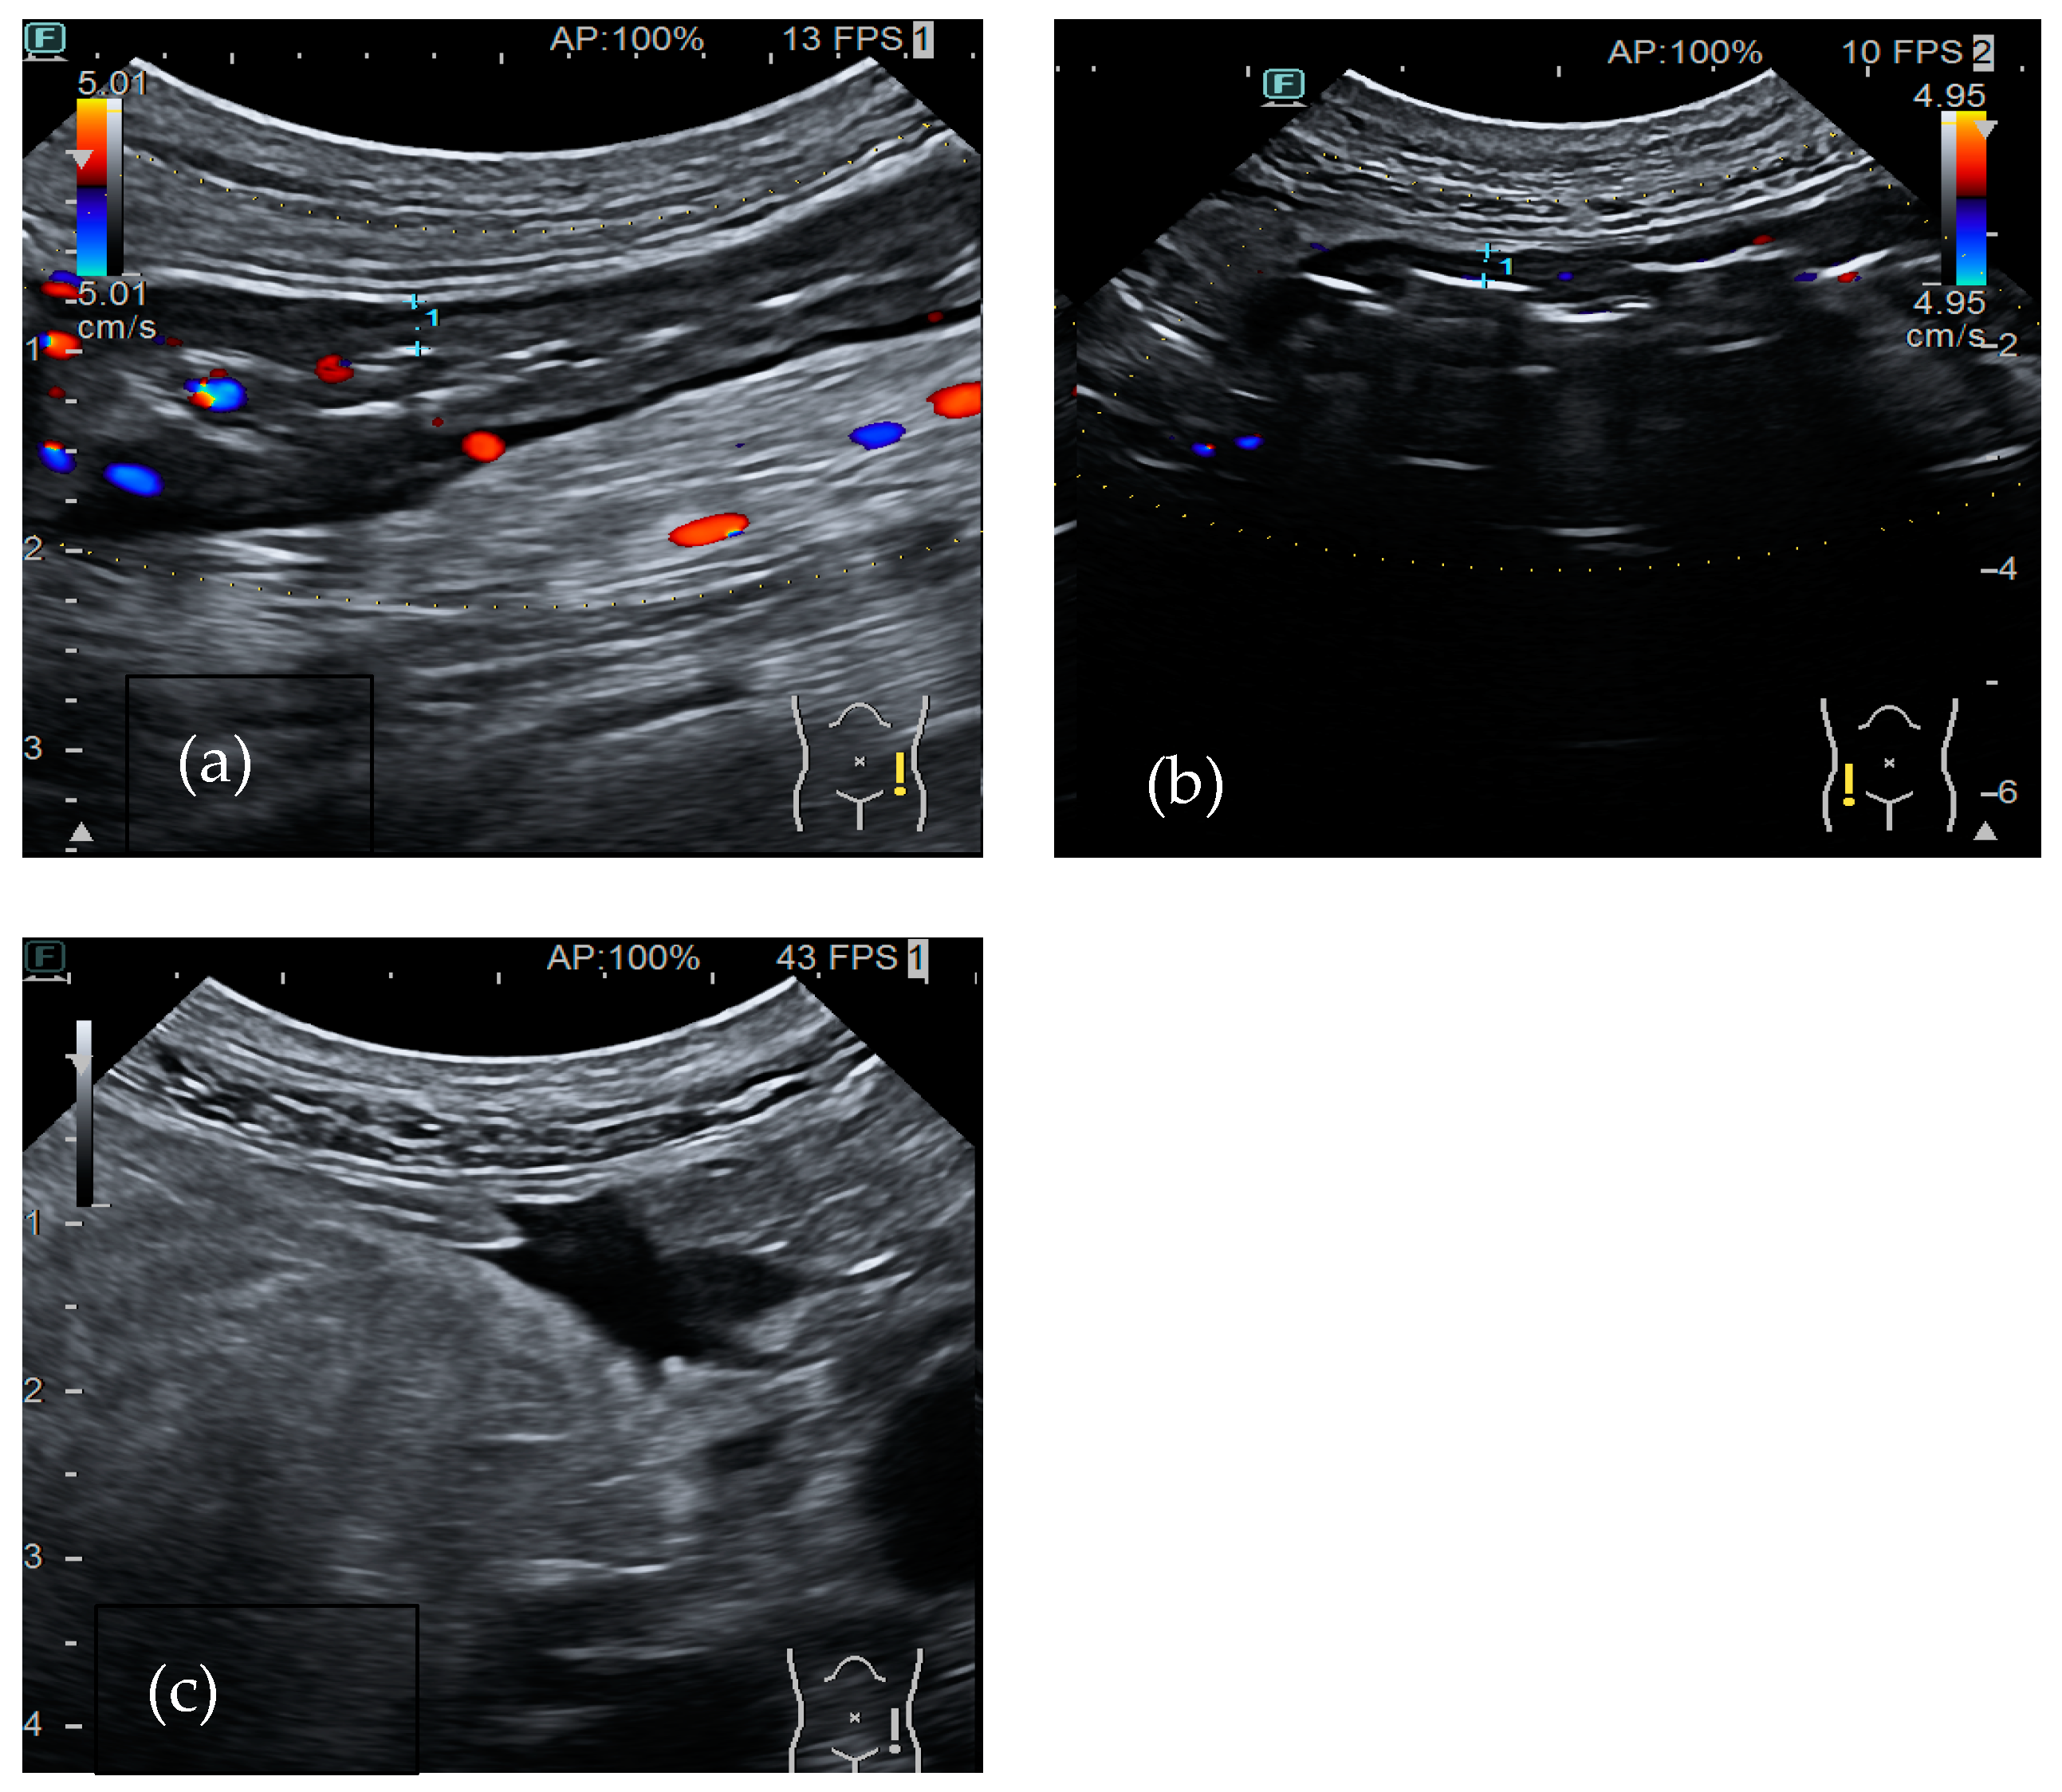

Salmonella and Campylobacter are Gram-negative bacteria responsible for self-limiting ileocecal infections. The typical involvement of terminal ileum and caecum determines acute right lower abdominal pain (Figure 1a,b). Diarrhea is absent or mild and stool cultures are not always requested; therefore, diagnosis is delayed. These symptoms are frequently considered as clinical signs of appendicitis and often lead to an unnecessary appendicectomy. US findings include marked hyperechoic thickening of the mucosa and submucosa of the terminal ileum and caecum with or without lymphadenopathy. Mesenteric fat and the appendix are not involved [31].

Figure 1.

A 37-year-old-man affected by Campylobacter infection. (a). Bowel ultrasound shows thickening of the right colon wall (5.8 mm) with active inflammation (color flow Doppler signals in both the bowel wall and surrounding mesenteric fat). (b). Presence of lymphadenopathy.